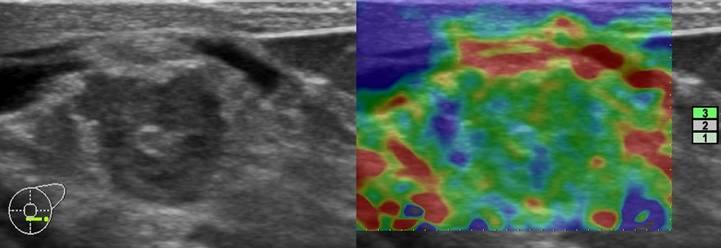

Ung thư vú

Ung thư vú - Ảnh 2

Ung thư vú - Ảnh 3

Ung thư vú - Ảnh 4

Ung thư vú - Ảnh 5

Ung thư vú - Ảnh 6

» Thông tin: Nữ giới – 69 tuổi.

» Lâm sàng: Kiểm tra sức khỏe.